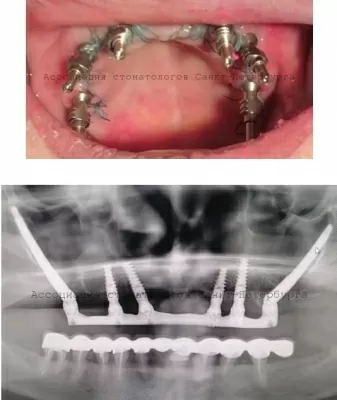

Дедушка у меня ветеран ВОВ и возраст у него такой уже, что хоть и молодится он, но ему уже из дома выходить сложно. Поэтому для протезирования нижней челюсти (случайно раздавил дедуля свою вставную челюсть) решили вызвать протезиста на дом, есть такая услуга в клинике Ассоциация стоматологов. Удобно: первый выезд на замер оплачивается по прейскуранту, а остальные приезды врач читать далее